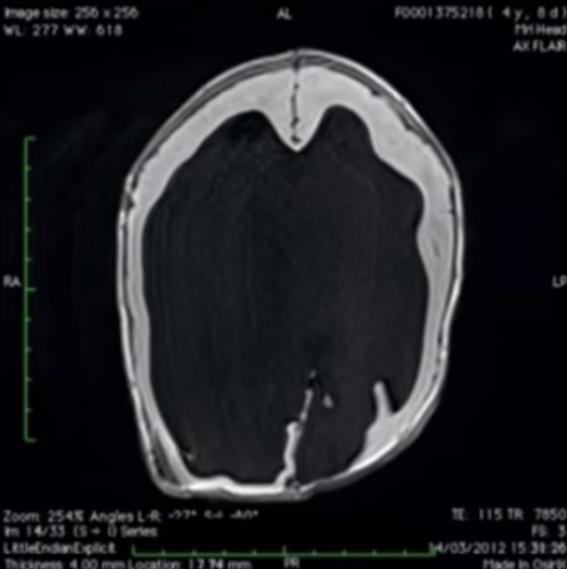

Ultrazvok je razkril, da se malčku nabira voda v lobanji, zaradi tega, pa mu tudi oteka.

Noah se je rodil s samo 2% možganov.

Niso vedeli kaj se dogaja... Dali so ga na rentgen in videli,

da so njegovi možgani močno zrasli.